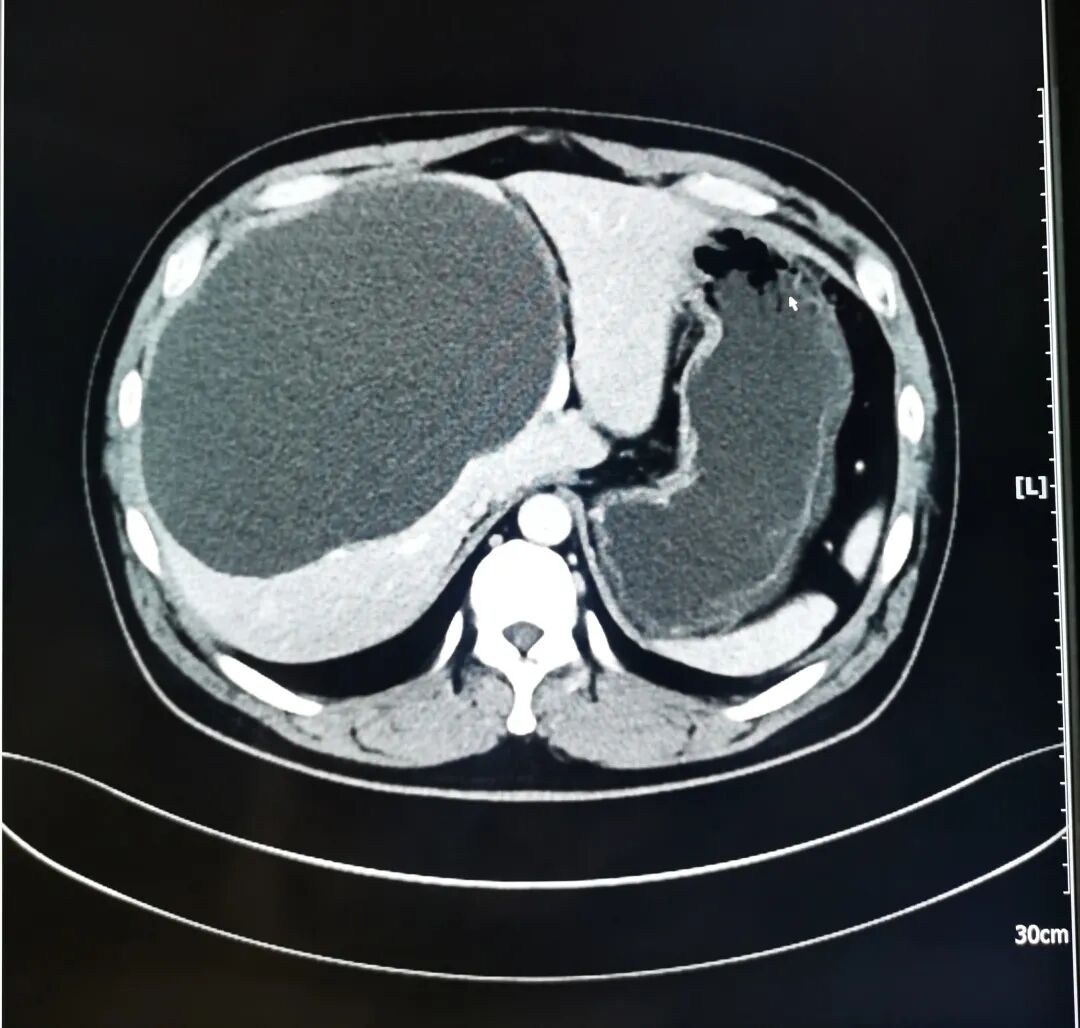

林先生入院后,副主任医师安艳新为其行CT检查,结果显示,林先生肝内多发囊肿,邻近组织受压、移位,其中较大的囊肿位于肝右叶,横截面为200mmX134mm,几乎占据整个右半肝